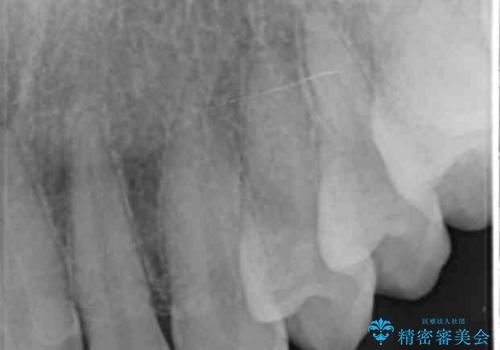

噛み合わせが深く、前歯の突き上げが大きいため欠けの繰り返しを防ぐべくセラミッククラウンによる補綴を行うこととしました。

- 「欠けてしまった前歯のコンポジットレジン修復をくり返していたが、すぐ外れてしまい困っている。」

、と前歯の欠けの改善を求めて来院されました。